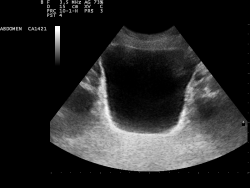

Ультразвуковое исследование мочевого пузыря выполняется с целью исключения заболеваний, при которых возникает недержание мочи и неадекватного опорожнения мочевого пузыря, на наличие последнего указывает сохранение мочи после мочеиспускания — остаточной мочи.